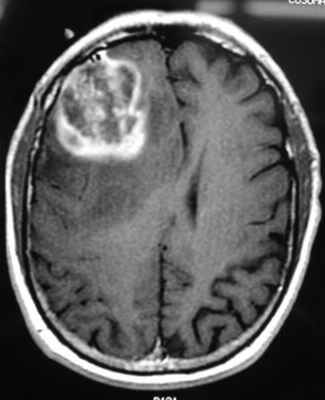

Глиобластома: симптомы, выявляемые с помощью МРТ. Аксиальный срез в режиме Т1 после контрастирования препаратом гадолиния демонстрирует распространенную опухоль правой лобной доли. Изображение предоставлено доктором George Jallo.